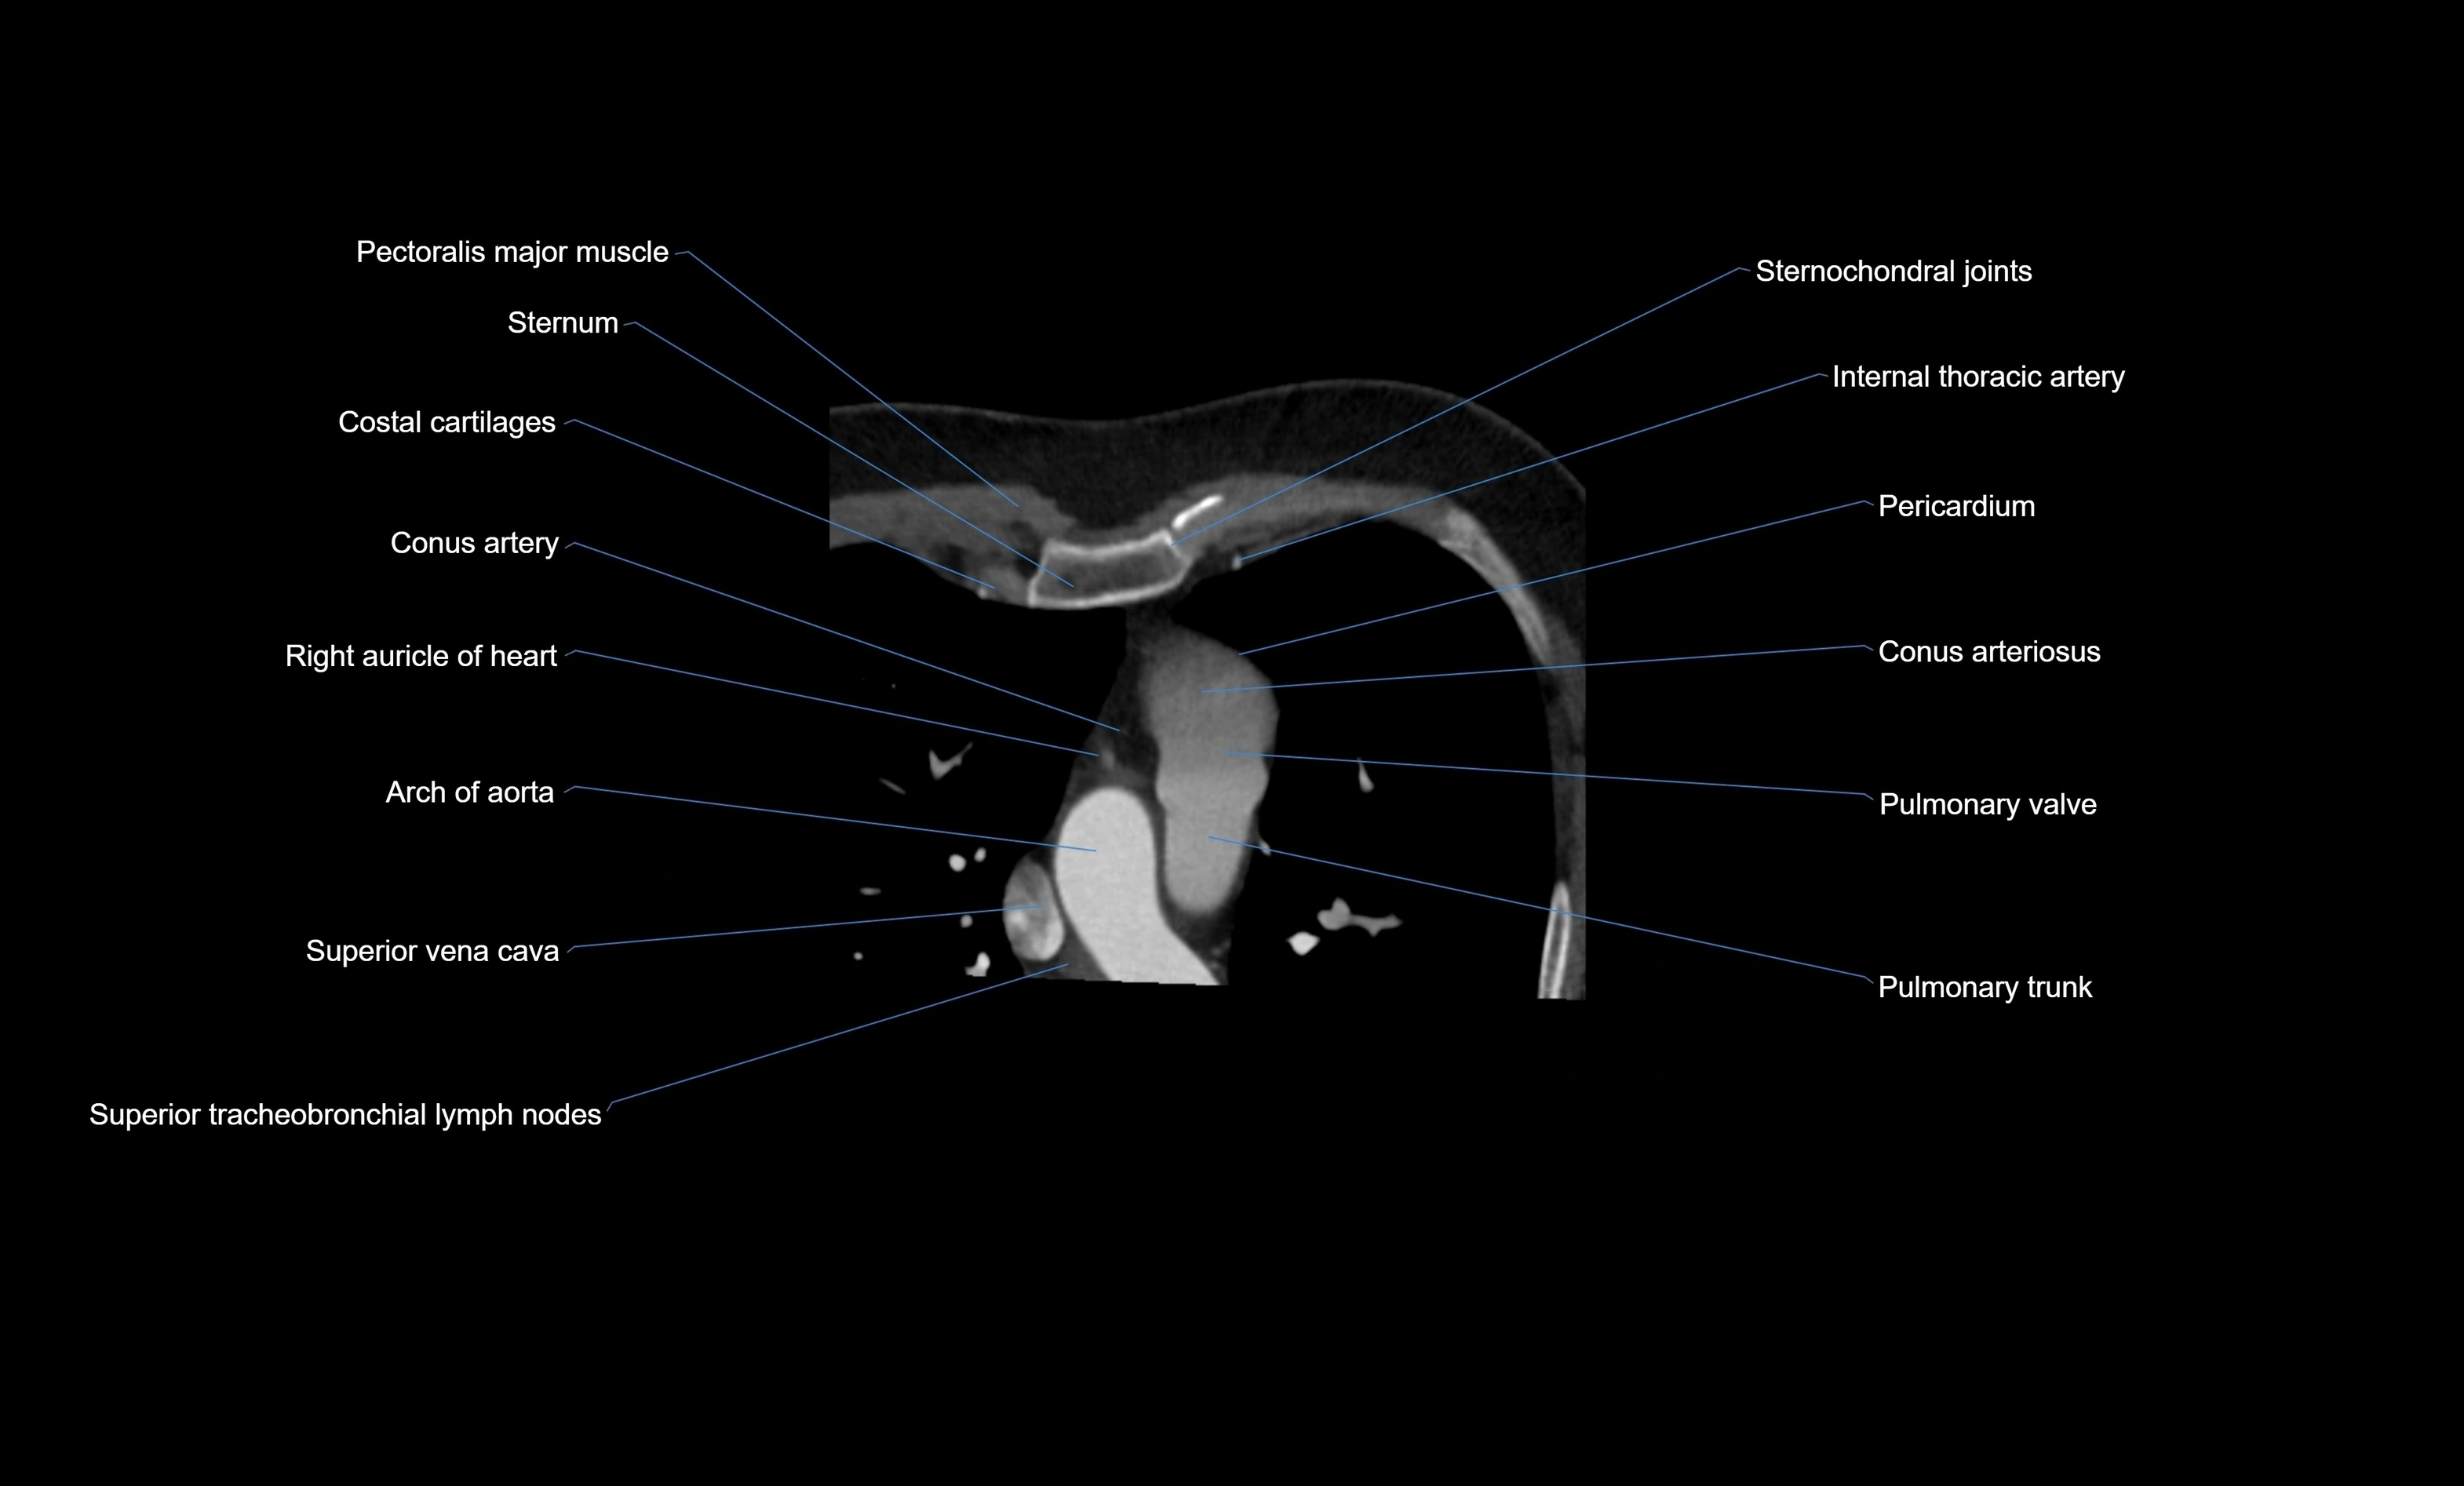

- Conus arteriosus

- Conus artery

- Pulmonary trunk

- Pulmonary valve

- Right auricle of heart

- Arch of aorta

- Superior vena cava

- Costal cartilages

- Sternum

- Pericardium

- Right internal thoracic artery

- Superior tracheobronchial lymph nodes